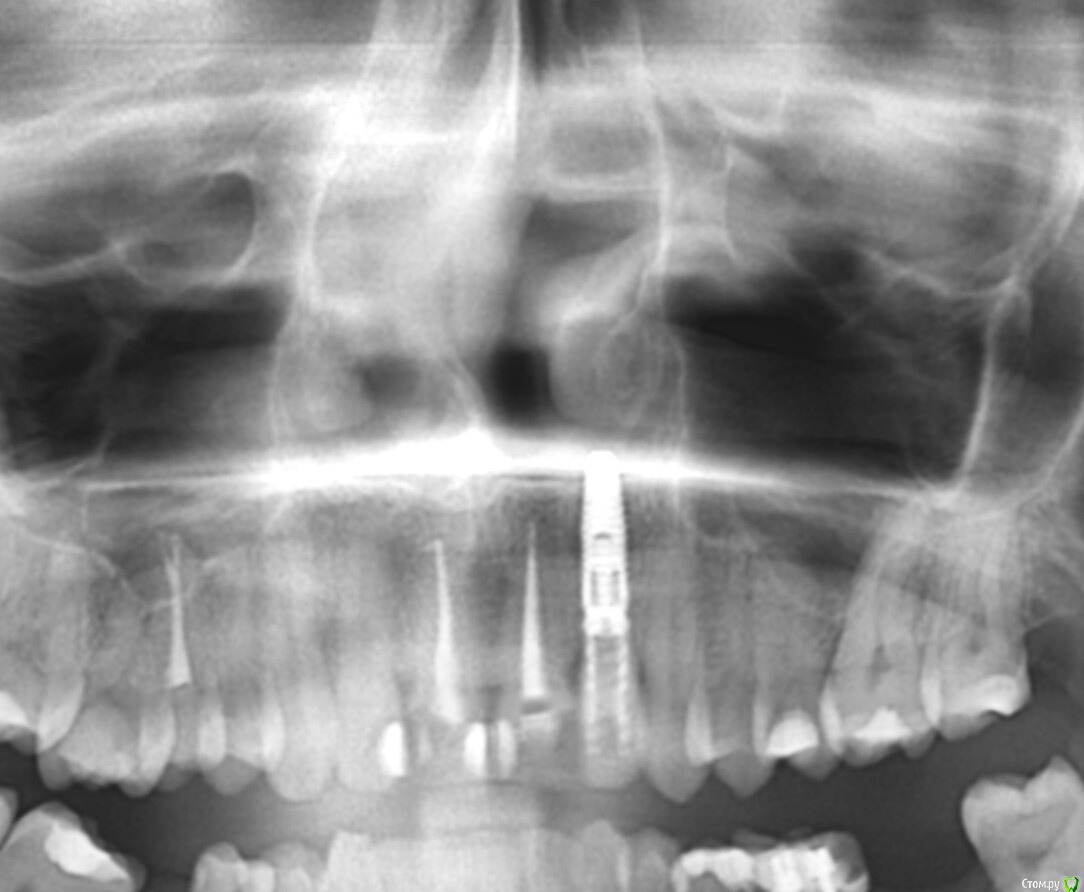

Julij Опубликовано 27 февраля, 2018 Автор Поделиться Опубликовано 27 февраля, 2018 (изменено) Все зависит от исходного количества тканей своего зуба и предпочтений доктора.Покажите свои снимки и фото, без этого ответить Вам невозможно спасибо за ответ.прикладываю снимок Изменено 27 февраля, 2018 пользователем Julij Ссылка на комментарий

St. Опубликовано 27 февраля, 2018 Поделиться Опубликовано 27 февраля, 2018 Перелеченные каналы выглядят хорошо.Из озвученных вариантов мне более подходящим кажется ДЦ, но рекомендую послушать еще мнения Ссылка на комментарий